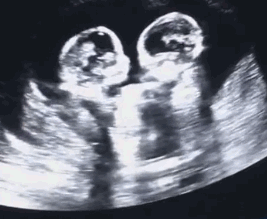

单胎和多胎的原因

多胎妊娠双胎的血HCG值一般会比单胎的高,但并不是说血值高就一定是双胎。目前单双胎的确诊,B超依然是金标准,并不能完全认为血值高就是双胞胎。